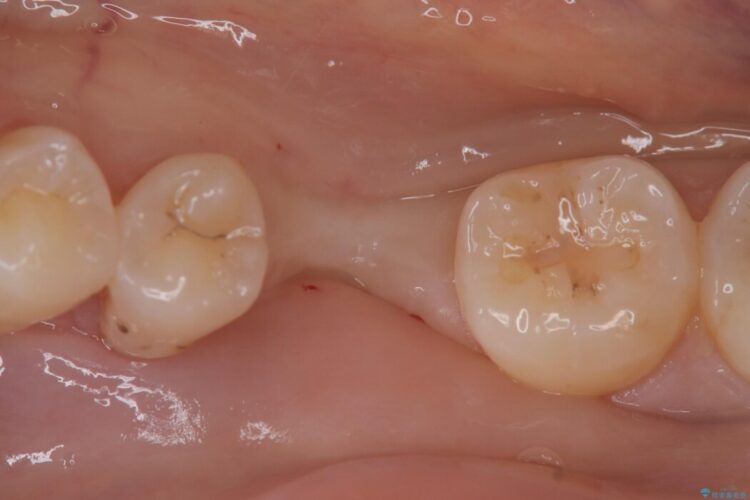

現在はインプラントが骨としっかり結合し、被せ物を装着して力強く噛めるようになっています。長期間の放置によって低下していた咀嚼機能が回復し、「もっと早く相談すればよかった」と喜んでいただけました。